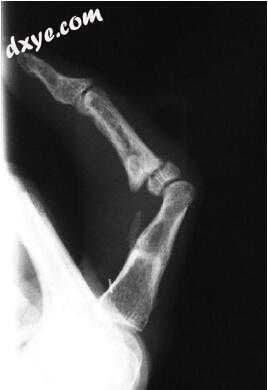

图23.42程序9:手术后2个月的X射线图像

图23.44程序11:手术后1年的X射线图像